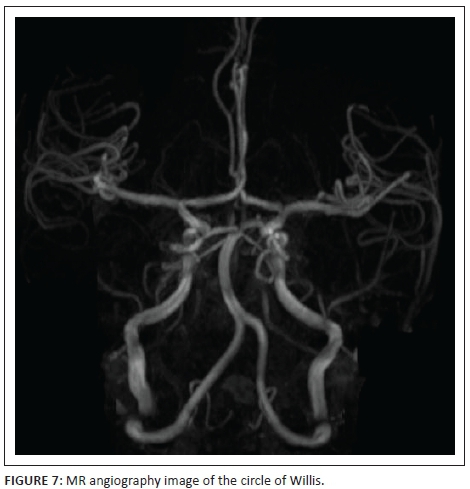

Magnetic resonance angiogram (MRA) was performed to ensure that the circle of Willis (Figure 7) was intact with no evidence of vasculopathy, particularly childhood vasculitis or transient cerebral arteriopathy. The MRA was normal, and importantly no aneurysms were noted.